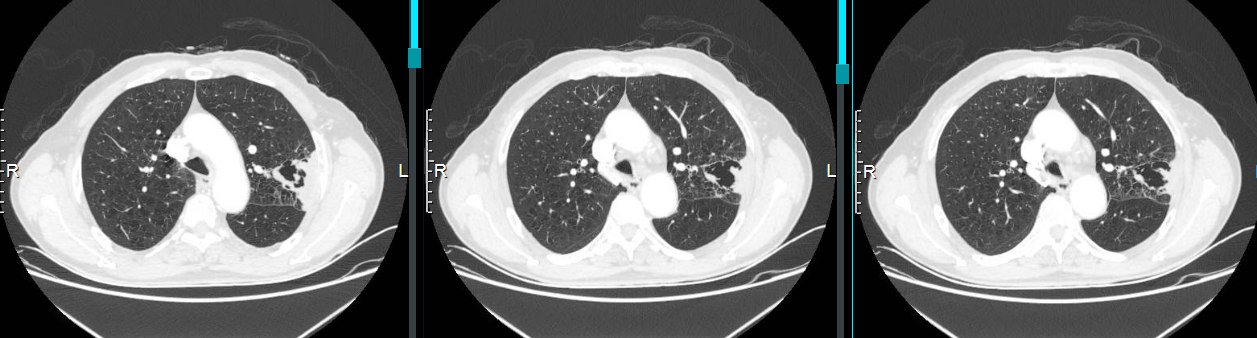

图2 2023.9.25肺部CT

入院诊断:1. 慢性阻塞性肺病伴有急性下呼吸道感染 2. 肺大疱 3. 高血压病3级(极高危) 4. 左上肺空洞原因待查

患者近8年反复因慢阻肺急性加重住院,期间多次行肺部CT(如下图)。

从上图可以看出,2015年开始患者持续随访肺部CT,2015年左肺可见“肺大疱”(不明显),2020年开始出现肺大疱样改变,随着随访时间的延长,肺大疱逐渐增大,且肺大疱周围可见肺组织实变影,外院多次行肺部CT考虑感染性空洞,那究竟这个在8年时间不断变化的“肺大疱”究竟是什么?